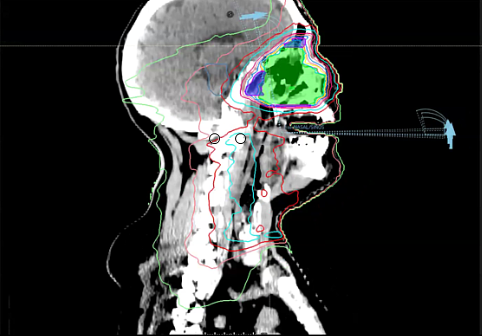

Elective Neck dose, Reirradiation, Carotid artery dose, 40Gy to neck, Pentoxyfylline and Vitamin E for neck Fibrosis, Neck failure rates, Submandibular Gland sparing, Review Dr. Sher’s plan, tongue tumor, dose versus volume, contralateral failure, oropharynx, drug trials, nasopharynx, volume desi...